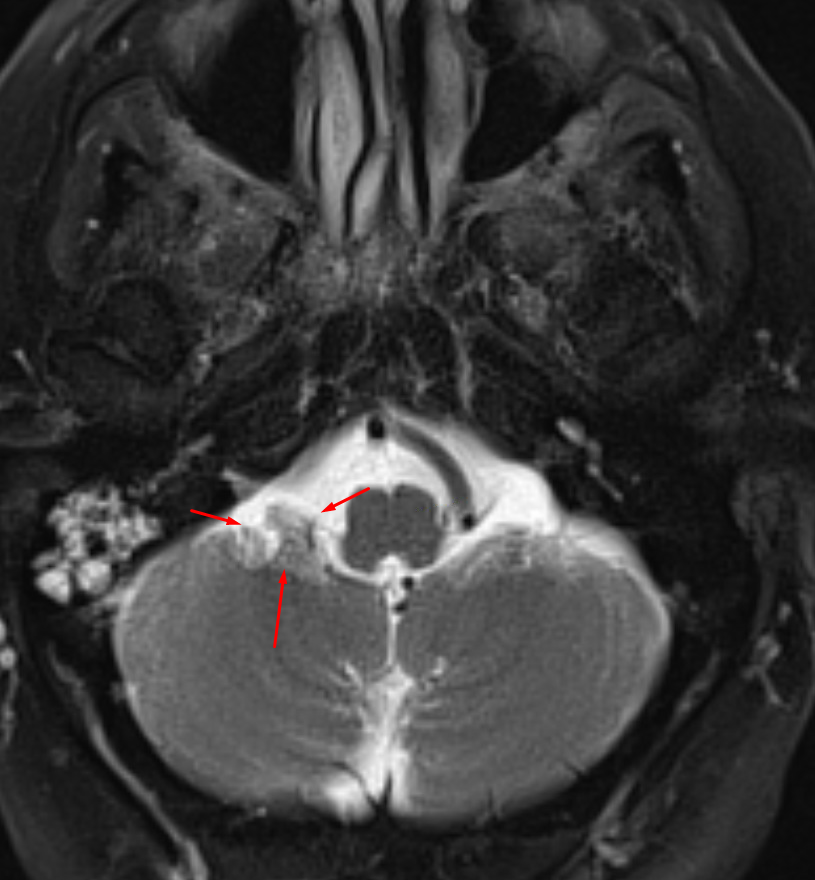

Age: 50

Sex: Female

Indication: Headache